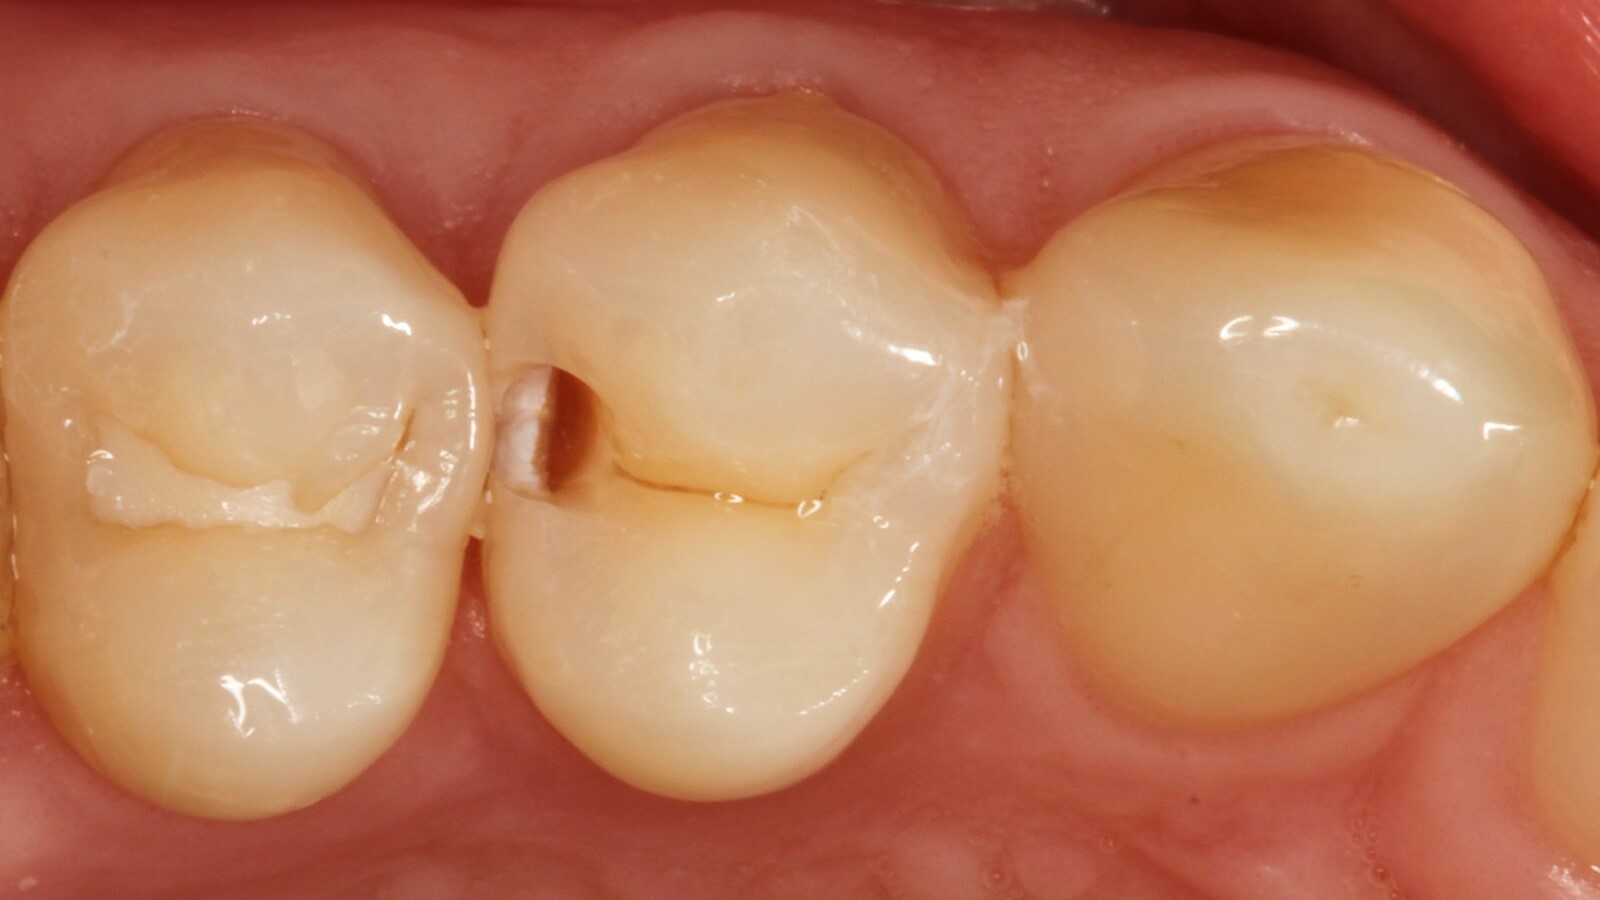

Le professeur Ernst a d'abord identifié les caries non visibles et a ouvert la lésion carieuse pour montrer le problème au patient (Fig. 1-2). Il a ensuite excavé la carie, préparé la cavité et placé une matrice sectionnelle (Fig. 3) avant de sceller la cavité avec de l'adhésif (Fig. 4). En une seule étape, il a rempli la cavité avec Venus Bulk Flow ONE (Fig. 5). Une fois la restauration terminée, le Pr Ernst l'a polie (Fig. 6) et a pris une radiographie de contrôle, qui montre également l'excellente radiopacité de Venus Bulk Flow ONE (Fig. 7).

L'un des principaux avantages de Venus Bulk Flow One est son processus d'application en une seule étape, qui permet de gagner du temps et de garantir des résultats cohérents. Ce composite ne nécessite pas de stratification, ce qui facilite son application en une seule étape. Venus Bulk Flow One peut être appliqué en couches allant jusqu'à 4 mm à l'aide de la technique Bulk Filling ou Bulk & Body. Le composite est facile à mettre en place grâce à son faible pouvoir adhésif et à son écoulement contrôlé. Une fois placé, le composite peut être polymérisé à l'aide d'une unité de photopolymérisation pour compléter le processus de restauration.